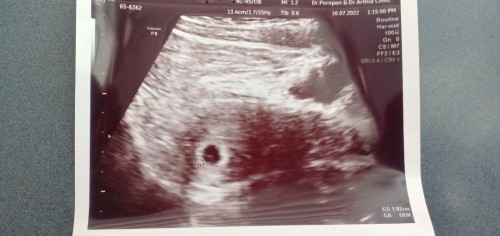

ท้อง6วีคถุง1.02เซนเล็กไหมคะ หมอบอกเจอถุงแต่ยังไม่เจอตัวค่ะ เรามีปวดฟหน่วงท้องเลยไปซาวด์ดู

1.02เซนถือว่าเล็กไปไหมสำหรับครรภ์6วีค

ทุกอย่างเริ่มตั้งแต่เล็กๆค่ะแม่ ใหญ่เลยน่าจะแปลก เพราะเค้าค่อยโตในนั้นเหมือนดักแด้😊